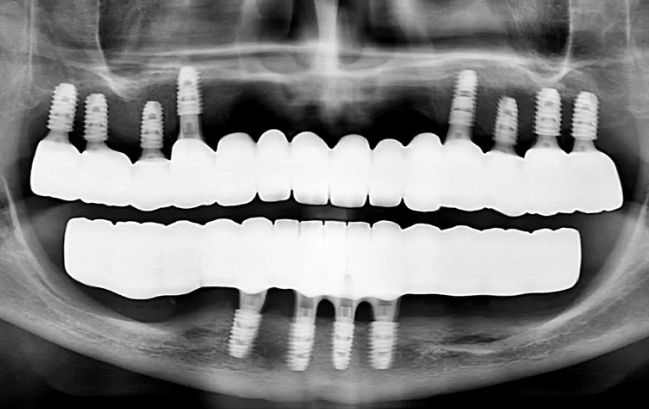

50대 남성, 원데이 수면 전체 임플란트 9개 식립